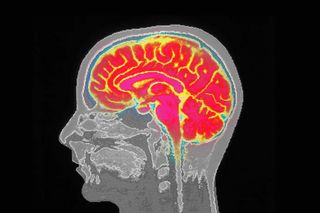

Anecdotally, a Covid19 infection is spoken in terms of how people experienced a loss of smell and inexplicable brain fog — a deficit in cognitive functioning that impacts memory in mysterious ways. Whilescientists have long speculated how the virus may change brain cells, new research offers conclusive proof of how even relatively mild cases of Covid19 are linked to tissue damage and loss in the brain region tied to the sense of smell — at least in the initial months since the infection.

The researchers looked at MRI scans taken both before and after participants contracted the coronavirus — making it a rare exploration. They invited 401 participants — whose health data was already logged into the U.K.’s Biobank — who had mild Covid19 during the first wave for a scan 4.5 months after their infection. Their scans were then compared with the 384 participants who had not contracted Covid19.

Notably, the scans revealed striking differences: the very size of the brain had shrunk after the infection, and the regions related to smell and memory had lesser grey matter. Even those who had recovered from Covid struggled to perform complex mental tasks — measured through what’s known as “executive function.”

“We were looking at essentially mild infection, so to see that we could really see some differences in their brain and how much their brain had changed compared with those who had not been infected was quite a surprise,” said lead author Gwenaelle Douaud, from the Wellcome Centre for Integrative Neuroimaging, at the University of Oxford. Douaud in an interview added that this extent of losing brain volume is “equivalent to at least one extra year of normal aging.”